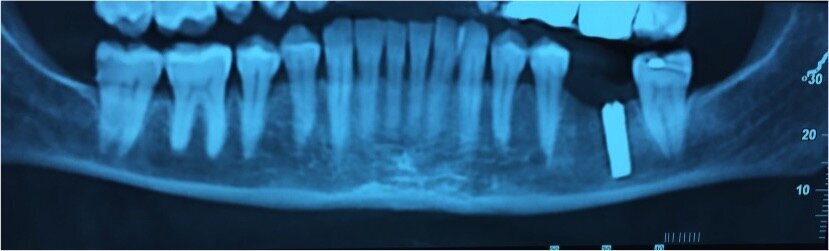

In seguito a cone beam postoperatoria viene rimossa la fixture e viene prescritta una terapia rivolta alla gestione dei sintomi. Quando la paziente giunge all’osservazione sono trascorsi circa dieci giorni dall’intervento di chirurgia implantare e una settimana dalla rimozione della fixture. All’osservazione della come beam l’impianto risulta inserito nel canale alveolare inferiore. La terapia prescritta prevede dobetin 5000 fiale, 1 al di’ per due settimane, lirica 75 mg, 1 compressa 2 volte al dì per una settimana, deltacortene 25 mg compresse, una compressa al dì per una settimana.